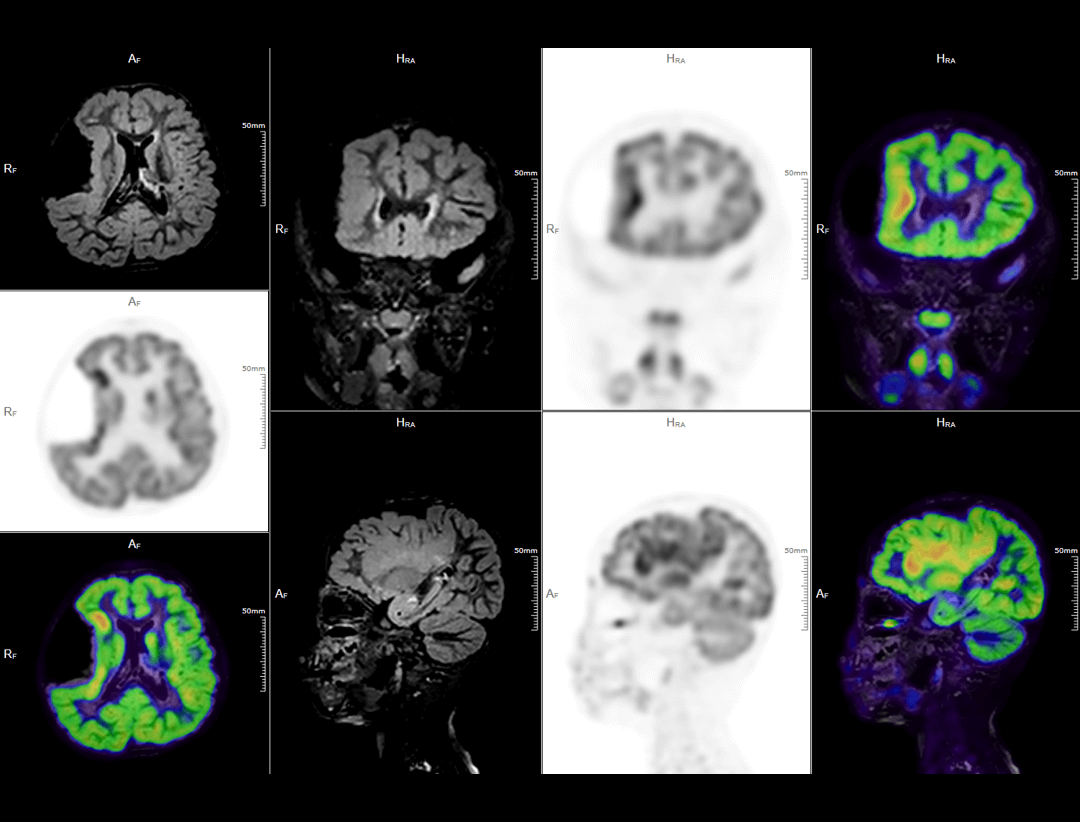

Neuro Imaging

The uSync research platform enables new levels of PET/MR research with simultaneous encoding of MR sequences, list-mode PET data, and physiological information into the same raw data stream, fulfilling space-time synchronization. This functionality facilitates new research opportunities, including simultaneous tracking of PET and MR tracers, simultaneous cardiac PET and MR, functional neurological PET/MR, and multi-parametric radiomics.